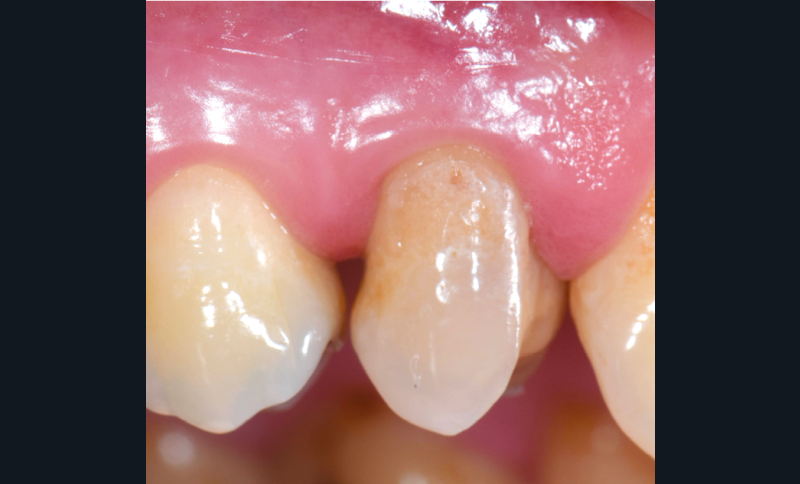

La solution soustractive par chirurgie : l’élongation coronaire

Longtemps considérée comme le « gold standard », cette technique bénéficie d’un recul clinique important et d’un haut niveau de preuve. En effet, elle permet de répondre aux objectifs d’accessibilité mais les inconvénients liés à cette technique (durée de traitement [9], coût tissulaire [10] et financier…) sont à mettre en balance avec les méthodes alternatives.

Lorsque l’indication est posée, le choix de la technique chirurgicale doit répondre à des contraintes anatomiques et esthétiques qui seront détaillées afin de choisir l’abord chirurgical adapté et ainsi maximiser les résultats (fig. 7 à 9).